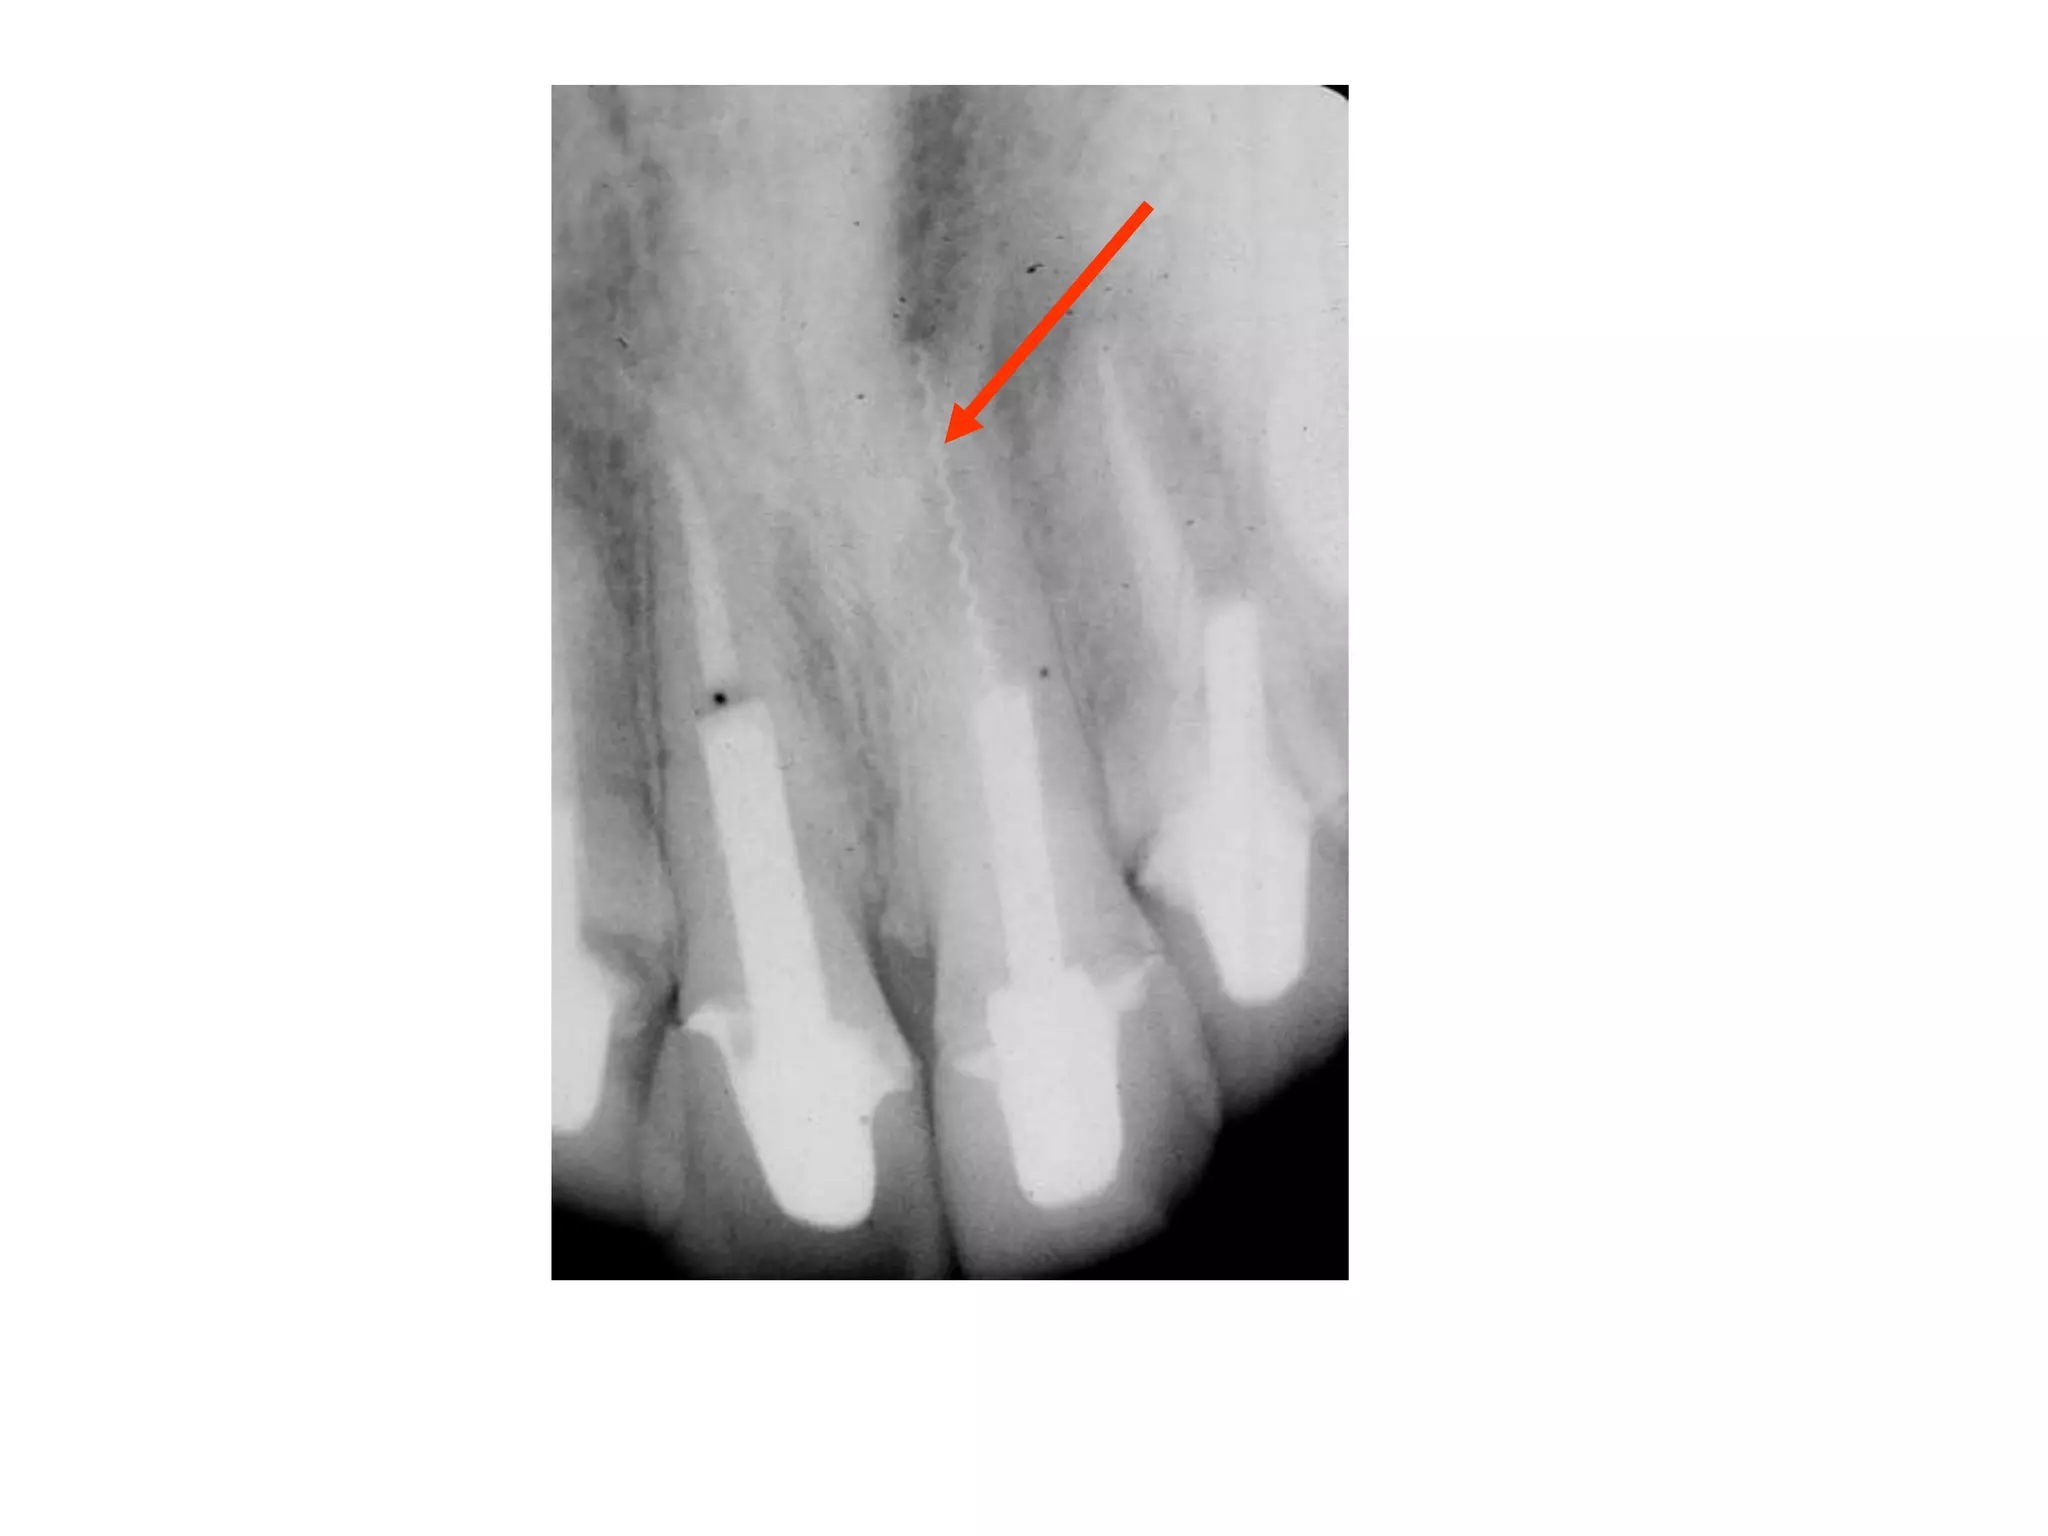

Moderate Adult Periodontitis

Horizontal bone loss or vertical

osseous defects

Total extent of bone loss not evident

May have slight mobility

(red arrows point to calculus)